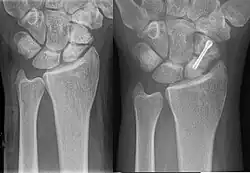

Eine Kahnbeinpseudarthrose ist eine Pseudarthrose vom Os scaphoideum des Handgelenks.

Das Kahnbein ist der biomechanisch wichtigste Knochen der Handwurzelknochen. Eine Kahnbeinpseudarthrose kann beim Ausbleiben der Bruchheilung einer Fraktur des Kahnbeines entstehen. Bei der konservativen, nicht operativen Behandlung werden Pseudarthroseraten von 23 % berichtet,[3] bei der operativen Behandlung wird in der Literatur von Pseudoarthroseraten zwischen 5 und 15 % berichtet.[4] Die Kahnbeinpseudarthrose hat somit im Wesentlichen zwei Ursachen:

Die Therapie erfolgt operativ, indem die Pseudarthrose entfernt wird und der dann verbleibende Defekt im Kahnbeinknochen mit einem Knochenspan aus dem Beckenkamm oder Knochenersatzmaterial stabilisiert wird (Operation nach Matti-Russe).[5][6][7] Zusätzlich kann eine Stabilisation mit einer Herbert-Schraube, die auch bei der Behandlung des Kahnbeinbruches eingesetzt wird, erfolgen.